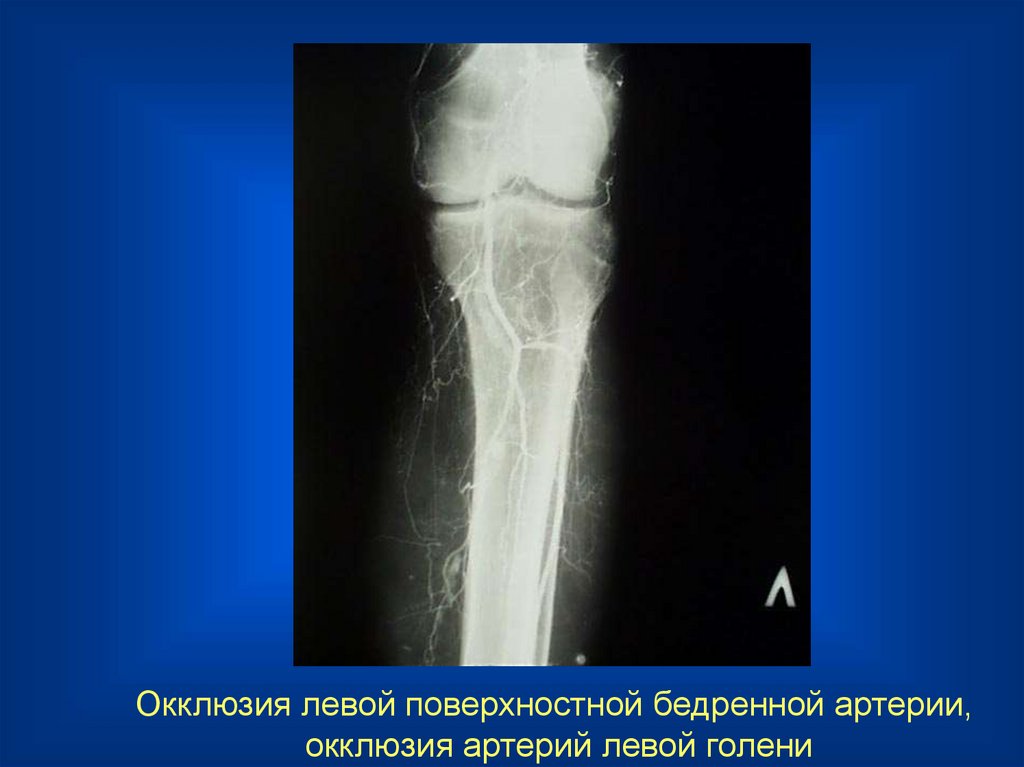

23.

Окклюзия левой поверхностной бедренной артерии,

окклюзия артерий левой голени

24.